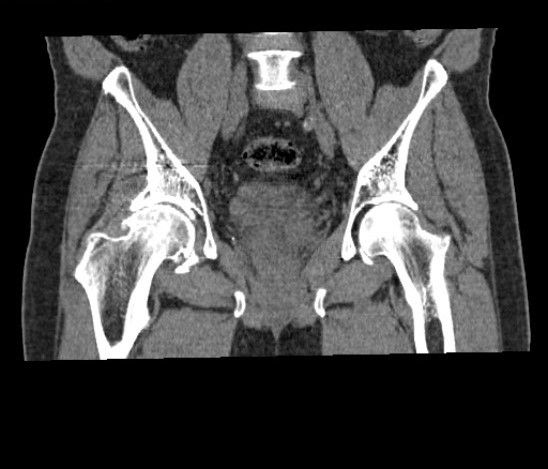

Exames de tomografia são muito confiáveis e seguros, realizados por aparelho de raios X de alta resolução que gira em torno do corpo, fazendo radiografias transversais. É capaz de obter imagens em fatias do corpo, gerando imagens tridimensionais. O exame é indolor, o paciente deve permanecer imóvel e é de rápida duração.